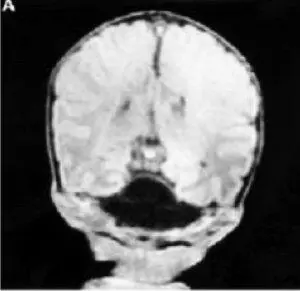

Рис. 17. Фотография и данные ЯМР ребенка с перманентным сахарным диабетом новорожденных и гипоплазией мозжечка (Hoveyda N. et al., 1999) [109]

В 1999 году была описана семья, имевшая 3 детей с перманентным сахарным диабетом новорожденных и гипоплазией мозжечка(Hoveyda N. et al., 1999) [109] (рис. 17). Установлен аутосомно-рецессивный тип наследования. Все дети не дожили до 1 года и погибли от метаболических расстройств, дыхательной недостаточности, сепсиса. Позже Sellick G. S. et al. (2004) [183] было установлено, что есть много специфических активаторов транскрипции, регулирующих экспрессию генов в β-клетках поджелудочной железы и нейронов.